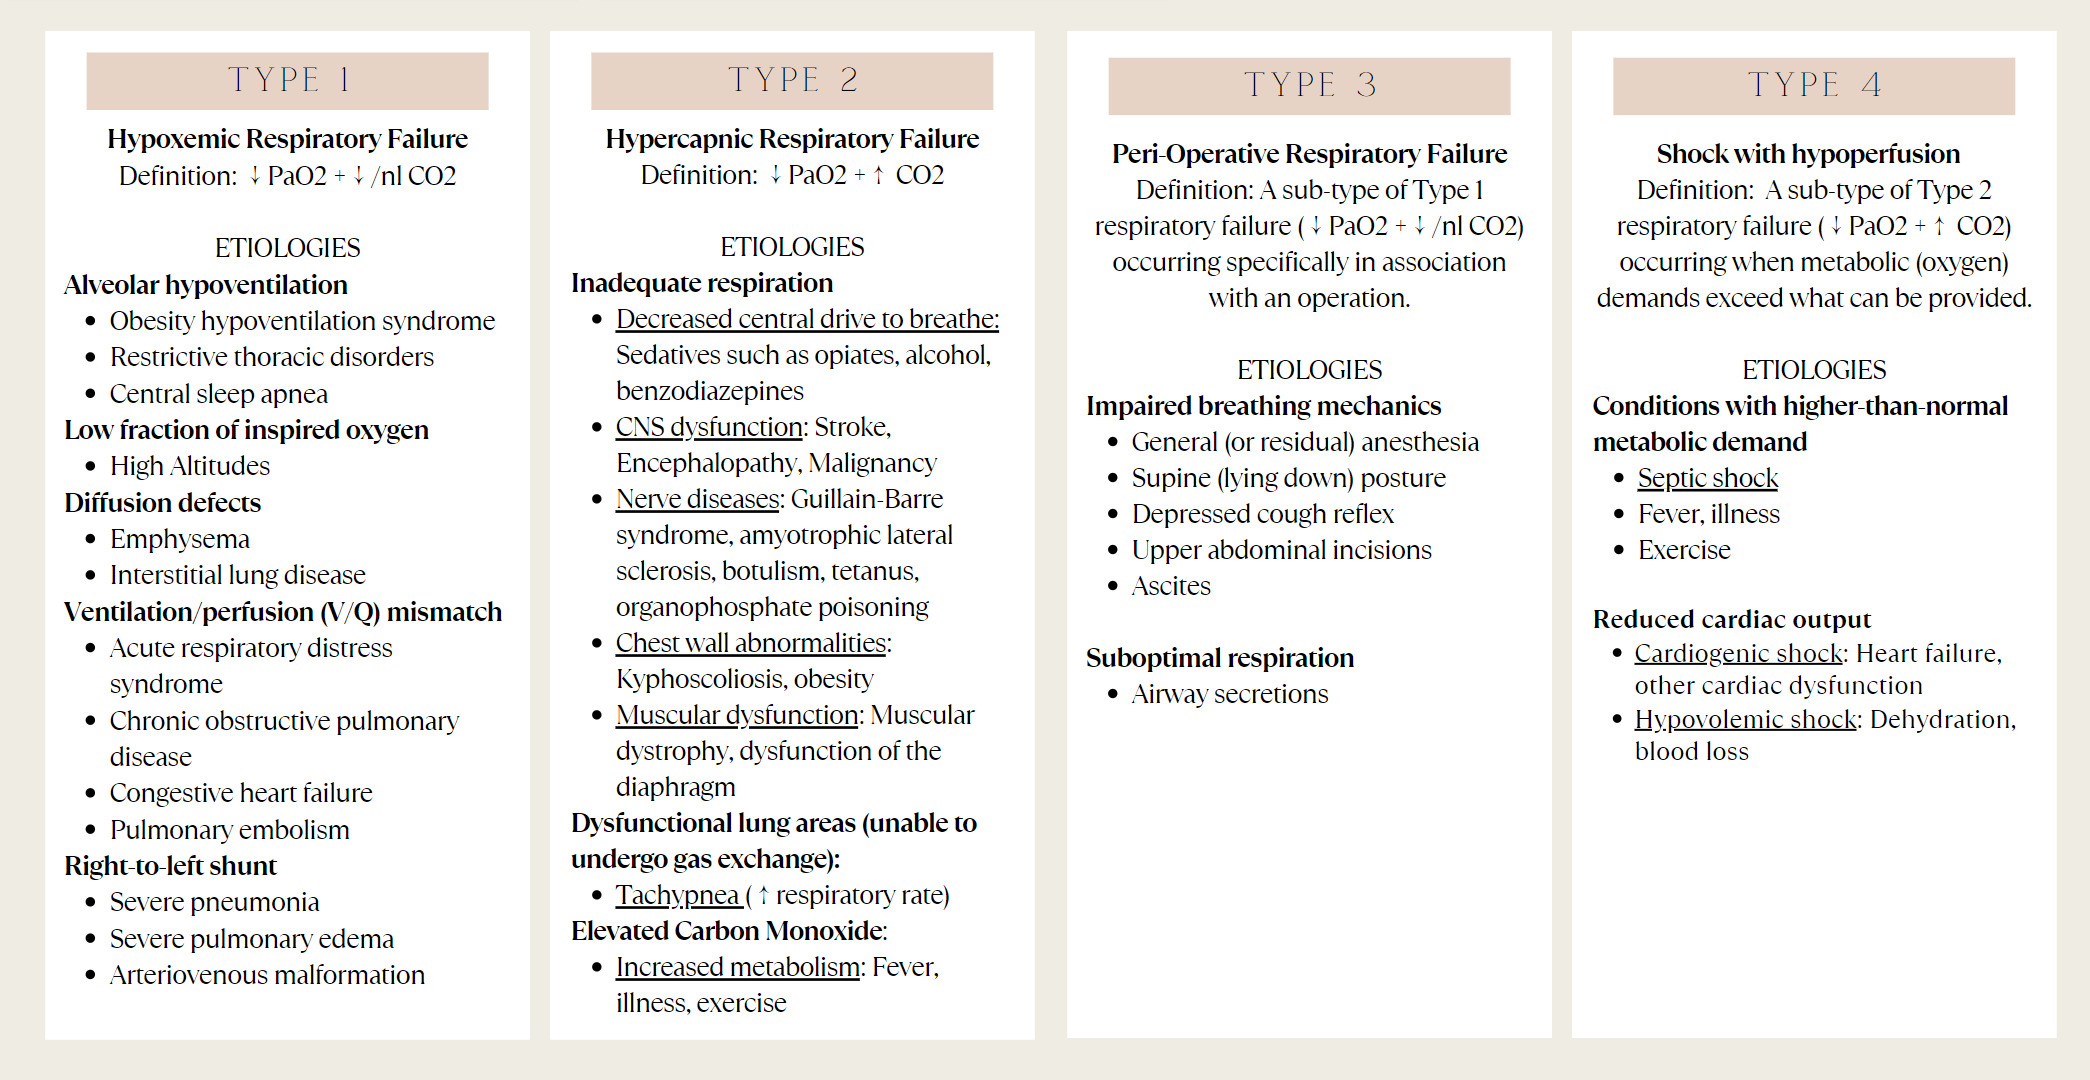

Respiratory failure can be of four types depending on their intensity levels;

Type I: – involves a ventilation/perfusion mismatch that causes untreatable hypoxemia (PaO2). Another characteristic of type I respiratory failure is alveolar flooding.

Type II: – involves alveolar hypoventilation resulting in hypercapnia (PaCO2). There is a significant reduction in the alveolar minute ventilation that entails inadequate removal of carbon dioxide.

Acute respiratory failure vs chronic respiratory failure: In type II respiratory failures, there is active vs chronic respiratory failure, active failure matures and progress over minutes to a couple days and involves respiratory acidosis (a condition where lungs are not able to get rid of all the carbon dioxide in the body). On the contrary, chronic failure takes anywhere from days to months to develop and involves a higher PaCO2 including increased levels of serum bicarbonate due to renal compensation.

Type III: – type III respiratory failure usually takes place in the peri or post operative period where the abdominal wall mechanics are abnormal. Patients usually have progressive atelectasis due to inadequate functional residual capacity leads to . The clinical progression of type III respiratory failure usually leads to either type I or type II respiratory failure.

Type IV: – is due to underlying circulatory collapse or shock (insufficient oxygen levels in the body) due to which patients are usually mechanically ventilated.

Causes of Respiratory Failure: can occur due to issues in any pathological or anatomical parts of the respiratory system.

- Central Nervous System – any condition that affects or lowers the conscious level.

- Peripheral Nervous System – any condition that affects the peripheral neural system (e.g. Guillain-Barré syndrome (GBS), nerve or spinal injury)

- Musculoskeletal System – any condition that affects the musculoskeletal part of the body (e.g. rib fractures, neuromuscular blockade)

- Airway Pathology – any condition that affects the airways (e.g. tumor, foreign body or laryngospasm)

- Pleural Pathology – any condition that affects the pleural parts of the lungs (e.g. haemothorax, pneumothorax or effusions)

- Pulmonary Pathology – any condition that affects the lungs (e.g. pulmonary fibrosis, pulmonary oedema, ARDS)

- Vasculature – any condition that affects vascular parts of the lungs (e.g. pulmonary embolism)